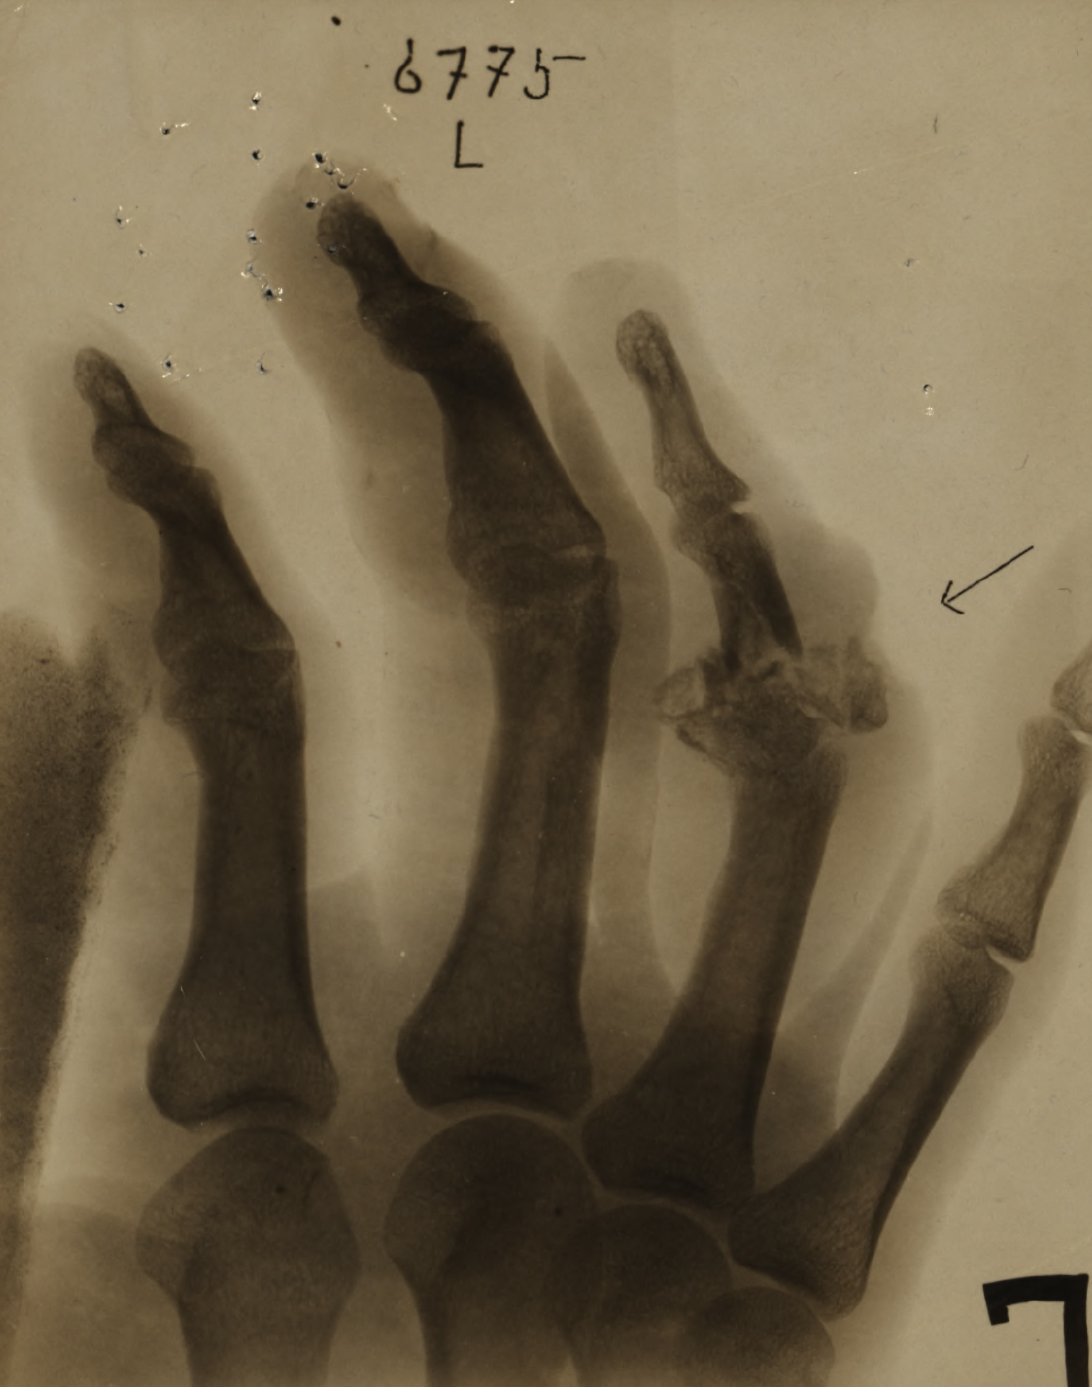

On 8 August 1918, Private Renaud received a GSW to his left hand and was admitted to No. 10 General Hospital the next day. He was then shipped to England aboard the A.T. Grantully Castle on 10 August 1918.